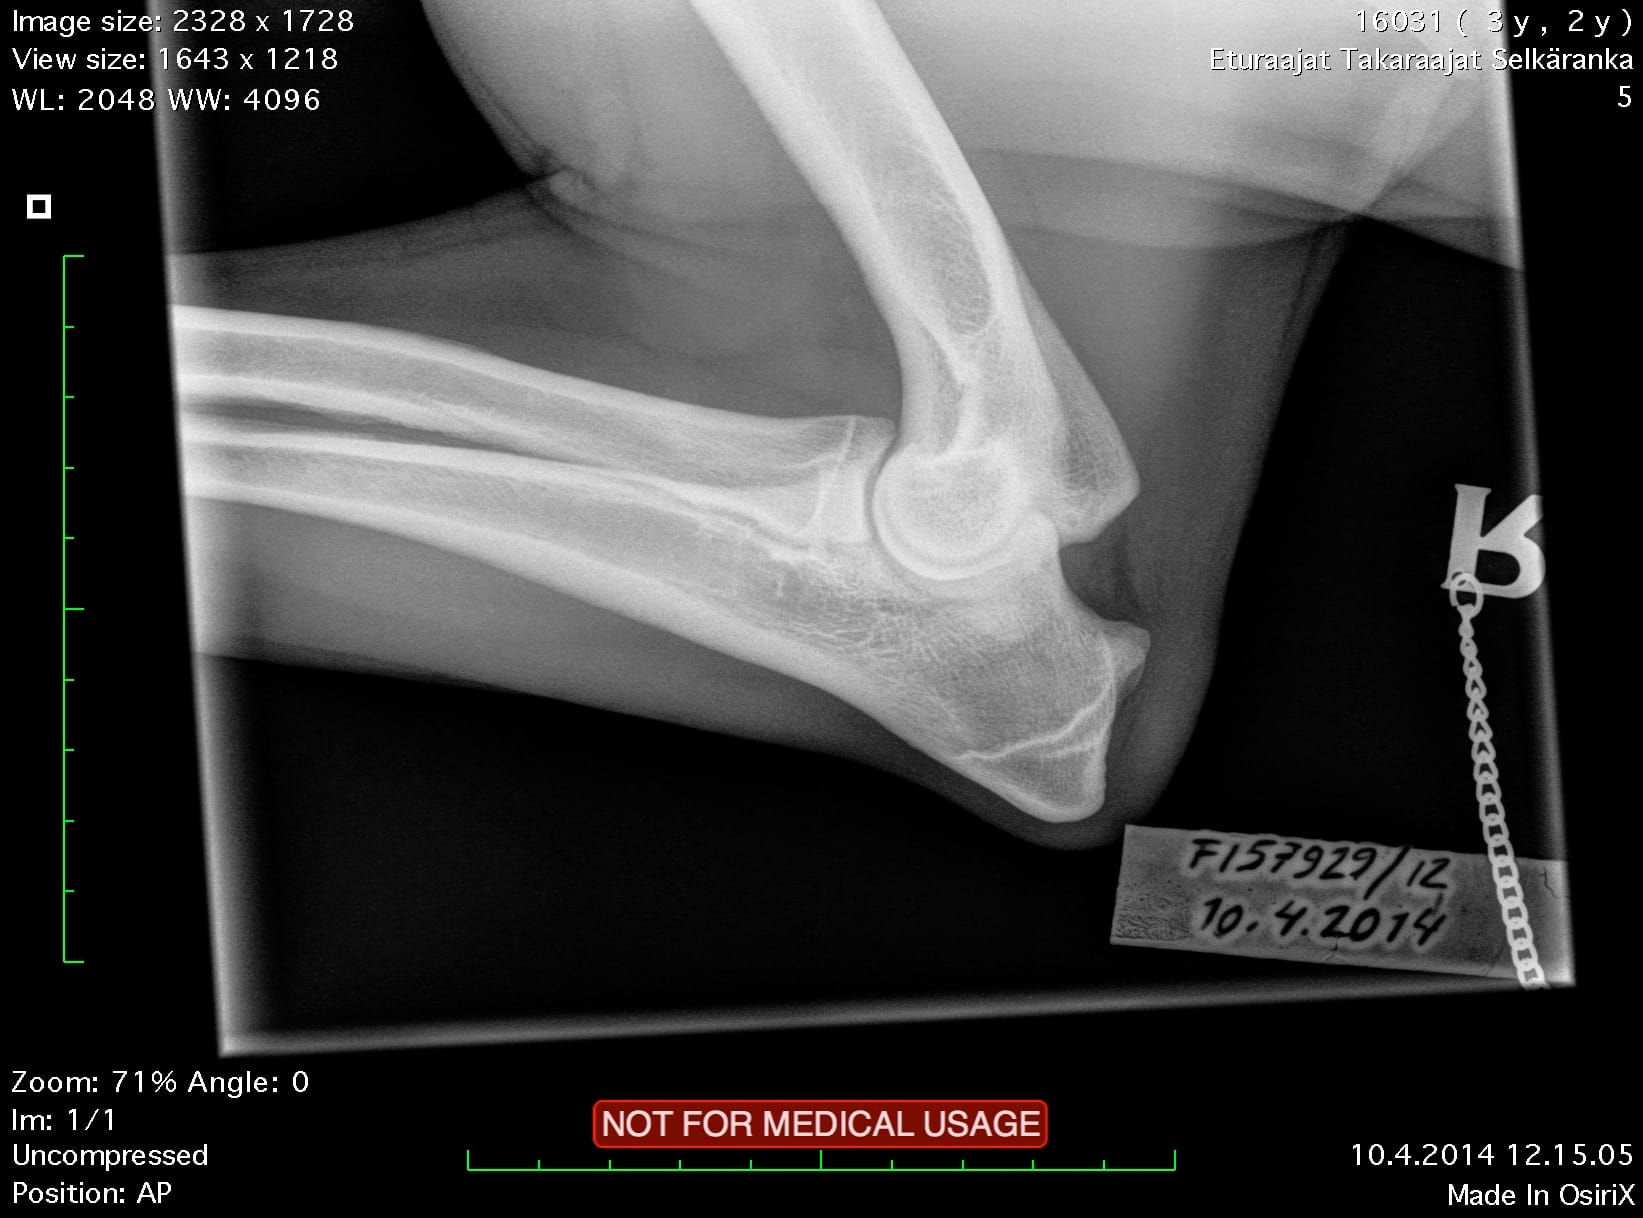

| Elbows: | 0/0 | |